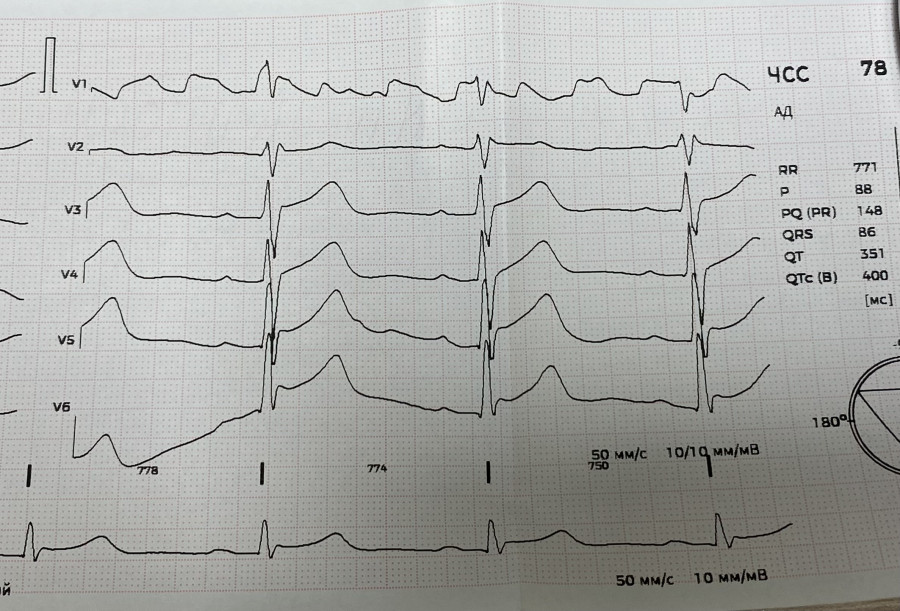

Динамика ЭКГ при гемоперикарде. До и после удаления крови.

Вложения:

IMG_8524.jpg

IMG_8524.jpg [ 2.78 MiB | Просмотров: 1850 ]

IMG_8525.jpg

IMG_8525.jpg [ 3.22 MiB | Просмотров: 1850 ]

IMG_8526.jpg

IMG_8526.jpg [ 2.19 MiB | Просмотров: 1850 ]

IMG_8527.jpg

IMG_8527.jpg [ 2.47 MiB | Просмотров: 1850 ]